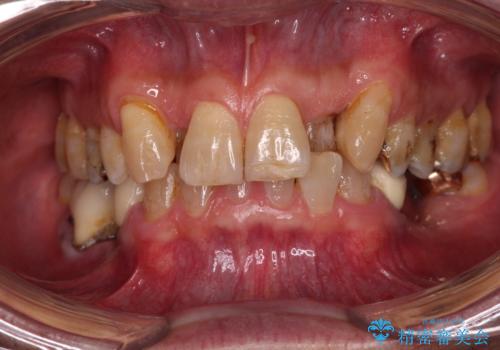

破折した奥歯 抜歯即時埋入インプラントによる補綴治療